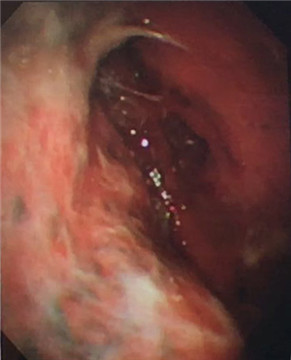

多發(fā)黃白色小結(jié)節(jié)

7月21日建立人工氣胸,擴(kuò)張肺部。7月22日,由周傳毅主任、張健主治醫(yī)師共同實施了胸腔鏡檢查,并活檢取出多處胸膜小結(jié)節(jié)。術(shù)后經(jīng)病理診斷,確診為結(jié)核性胸膜炎。檢查過程無任何不適,后續(xù)配合抗結(jié)核藥物治療,王爺爺恢復(fù)良好,已出院返家。

我院呼吸內(nèi)科采用改良型“軟式胸腔鏡”,該新設(shè)備軟硬結(jié)合,前端可彎曲,能多方向觀察胸腔內(nèi)改變,比老式“硬式胸腔鏡”的探查視野更大,診斷更準(zhǔn)確。